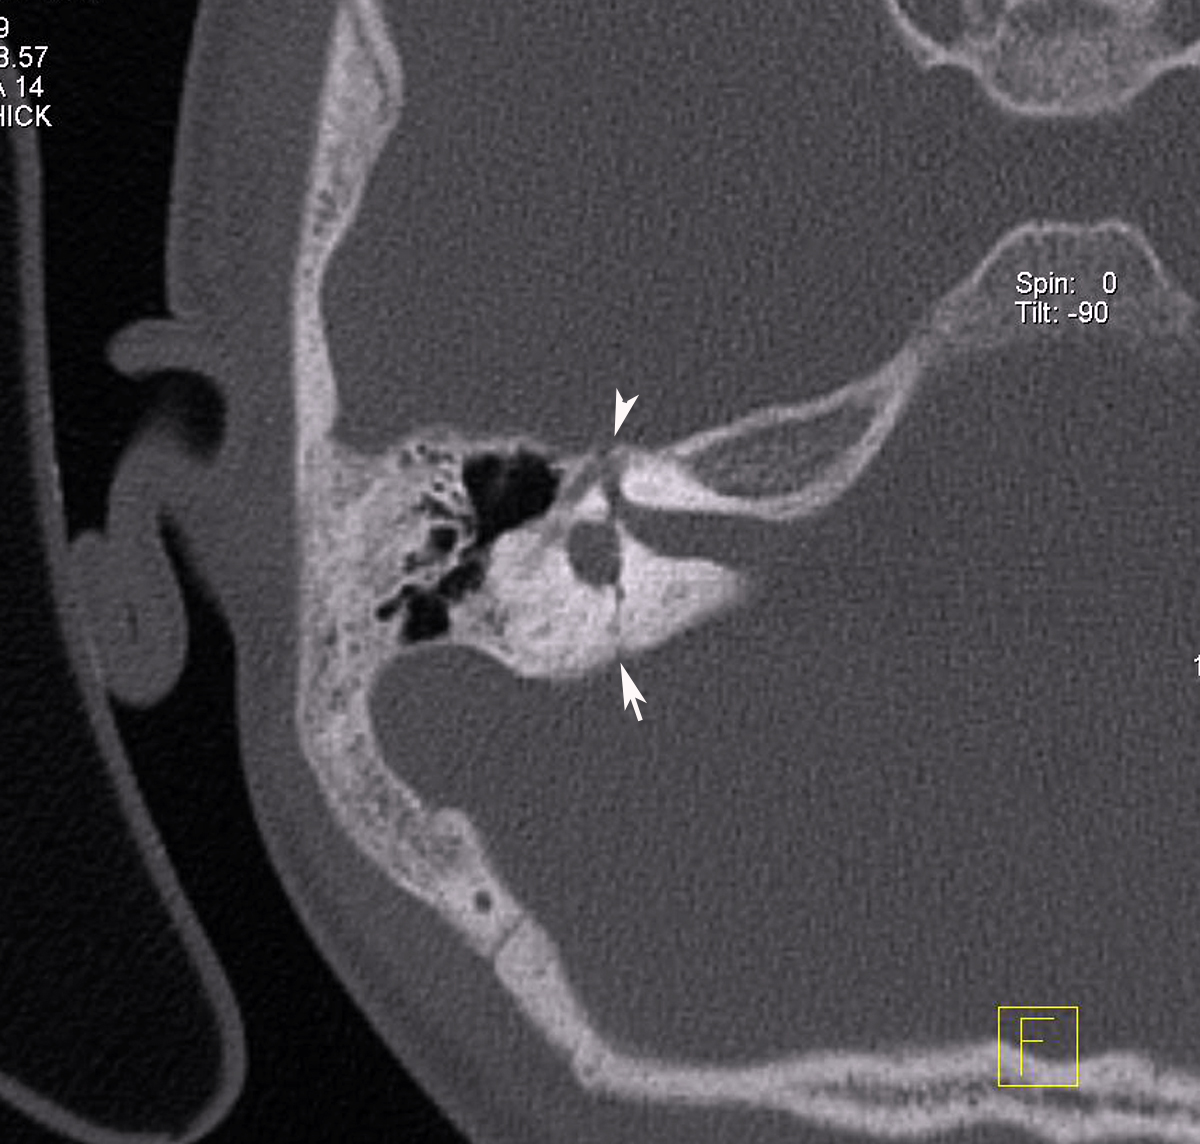

Симптомы продольного перелома височной кости

Симптомы продольного перелома височной кости 116 фотографий